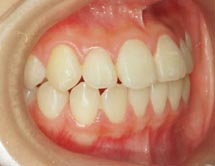

2.上顎前突(出っ歯) 上の前歯がかなり出ていています

治療前